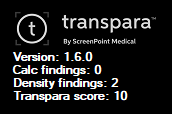

Support ScreenPoint Transpara CAD

The viewer supports ScreenPoint’s Transpara CAD objects.

The CAD header with the Transpara logo contains the number of calcification and mass findinds, the algorithm version and the Transpara score (integer value between 0 and 10).